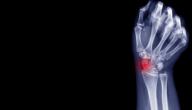

ما هو التهاب المفاصل؟

يمكن أن يؤثر التهاب المفاصل على مفصل واحد أو أكثر في الجسم، ويوجد أكثر من 100 نوع منه، وتختلف هذه الأنواع في أسبابها وطرق علاجها، واثنان من أكثر الأنواع شيوعًا هما التهاب المفصل التنكسي والتهاب المفاصل الروماتويدي، وعادةً ما تتطور أعراض التهاب المفاصل مع مرور الوقت، إلا أنها قد تظهر فجأةً عند البعض، ويُعدّ هذا الالتهاب أكثر شيوعًا عند الأشخاص البالغين الذين تزيد أعمارهم عن 65 عامًا، كما أنه أكثر شيوعًا عند النساء مقارنةً بالرجال.[١]

ما هي أعراض الإصابة بالتهاب المفاصل؟

تختلف أعراض التهاب المفاصل اعتمادًا على النوع الذي يعاني منه الشخص، وتتضمن الأعراض العامة ما يأتي:[٤]

• آلام المفاصل وحساسيتها تجاه اللمس وتصلبها.

• تقييد حركة المفاصل.

• احمرار ودفء في الجلد في منطقة المفصل المصاب.

• ضعف العضلات.